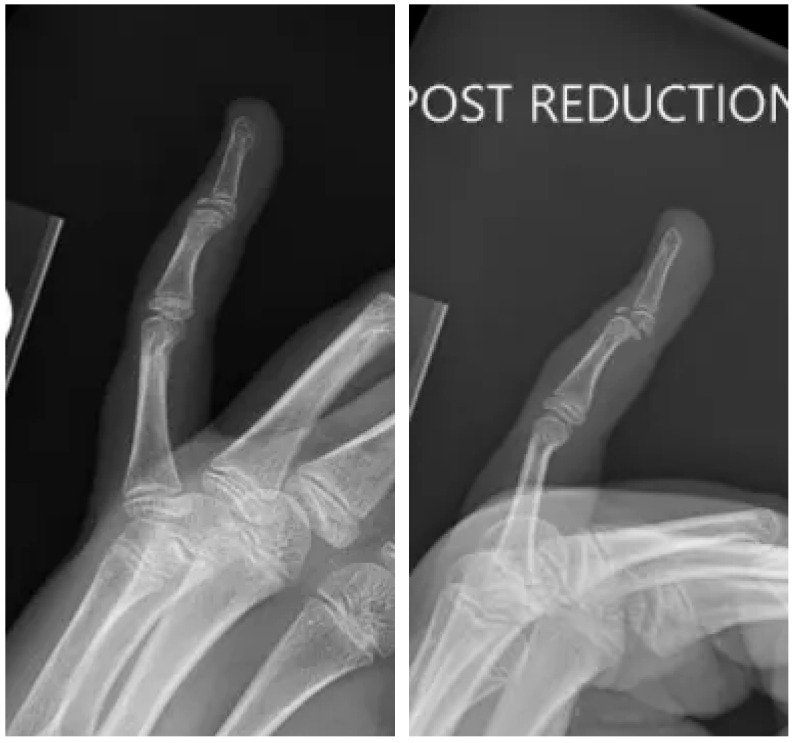

手指损伤在儿科患者中很常见,保守治疗通常愈合良好。然而,罕见的骨折类型涉及明显的移位和物理损伤,如本例所述,需要专门的手术干预,以确保适当的愈合和防止长期并发症。病例介绍:一名12岁的女性,以左手为主,表现为左第五指过伸后的远端指间关节疼痛、肿胀和畸形。最初的x线片显示掌侧移位的关节内骨折伴物理受累,经计算机断层扫描(CT)成像证实。保守治疗与闭合复位和夹板未能达到适当的对准。手术干预通过背侧入路进行,利用ORIF与k针固定来恢复关节一致性并确保解剖对准。结果:术后随访显示满意的愈合,保持复位,疼痛缓解,无并发症。患者以最小的僵硬度恢复了手指的功能使用,生长板在恢复期间未受累。讨论:本病例强调了先进影像学、早期转诊和量身定制的手术干预对罕见槌状骨折伴掌侧移位和物理损伤的重要性。在这个复杂的病例中,ORIF提供了可靠的稳定和最佳的结果。结论:掌侧移位的Salter-Harris III型DIP关节骨折是儿科患者罕见且具有挑战性的损伤。该病例强调了ORIF在获得成功结果中的作用,并强调了精确复位和稳定以防止长期并发症的重要性。

Introduction: Finger injuries are common in pediatric patients and typically heal well with conservative management. However, rare fracture patterns involving significant displacement and physeal injury, such as the one described in this case, require specialized surgical intervention to ensure proper healing and prevent long-term complications. Case Presentation: A 12-year-old left-hand-dominant female presented with pain, swelling, and deformity at the distal interphalangeal (DIP) joint following hyperextension of the left fifth digit. Initial radiographs revealed a volar displaced intra-articular fracture with physis involvement, confirmed by computed tomography (CT) imaging. Conservative management with closed reduction and splinting failed to achieve adequate alignment. Surgical intervention was performed via a dorsal approach, utilizing ORIF with K-wire fixation to restore joint congruity and ensure anatomic alignment. Outcomes: Postoperative follow-up demonstrated satisfactory healing, maintained reduction, and resolution of pain with no complications. The patient regained functional use of the digit with minimal stiffness, and the growth plate remained uninvolved during the recovery period. Discussion: This case underscores the importance of advanced imaging, early referral, and tailored surgical intervention for rare mallet fractures involving volar displacement and physeal injury. ORIF provided reliable stabilization and optimal outcomes in this complex case. Conclusions: Volar displaced Salter-Harris III fractures of the DIP joint are rare and challenging injuries in pediatric patients. This case highlights the role of ORIF in achieving successful outcomes and emphasizes the importance of precise reduction and stabilization to prevent long-term complications.